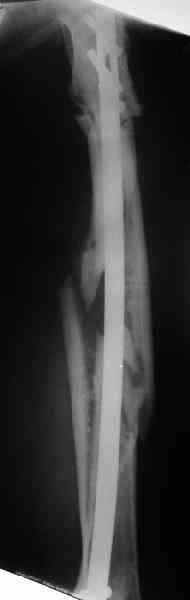

Надо делать чрескожную подвертельную остеотомию, чтобы получился открытый клин. Проблемы будут и с формированием канала, надо развертки типа наших. Был как-то похожий случай, сделали одномоментно, сняли аппарат 5-месячый на столе, заштифтовали с подвертельной остеотомией (в приложении).